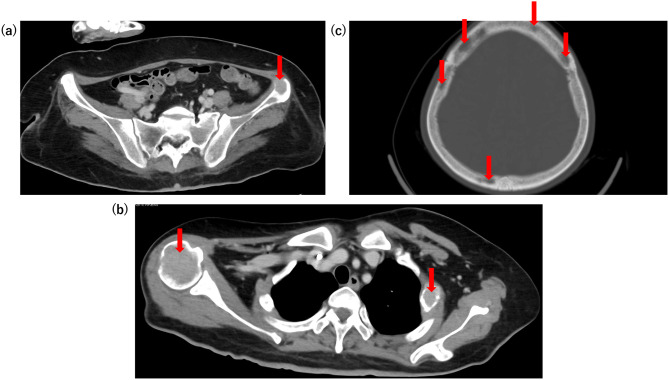

Case presentation: A 54-year-old Japanese woman with severe hypercalcemia (serum total calcium concentration of 23.0 mg/dL) was referred to our hospital. Initial management included multiple sessions of emergency hemodialysis, aggressive hydration, and administration of calcitonin. Although these interventions temporarily improved her condition, her serum calcium levels soon rebounded. The addition of bisphosphonates did not induce a prompt or sufficient reduction in serum calcium levels. Computed tomography revealed osteolytic lesions, strongly suggestive of malignancy. Given that the pathological condition was attributed to bone lesions, denosumab was administered, leading to a marked reduction in serum calcium levels and sustained control. A definitive diagnosis of DLBCL was established through bone biopsy and bone marrow aspiration. Based on these findings, severe hypercalcemia was determined to be secondary to DLBCL with multiple bone lesions. Following the initiation of chemotherapy, her serum calcium levels remained stable during follow-up.